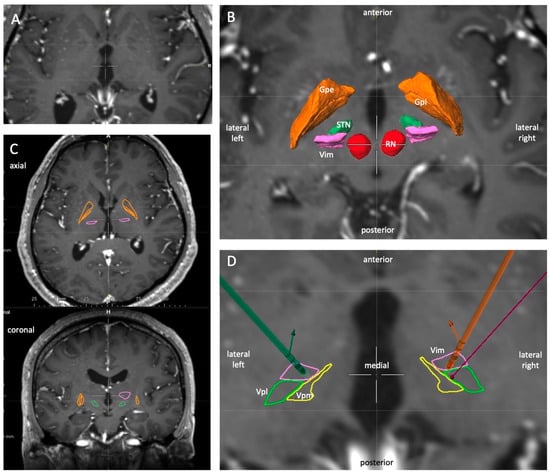

2.2. Preoperative Planning

3.1. Lead Location and Orientation